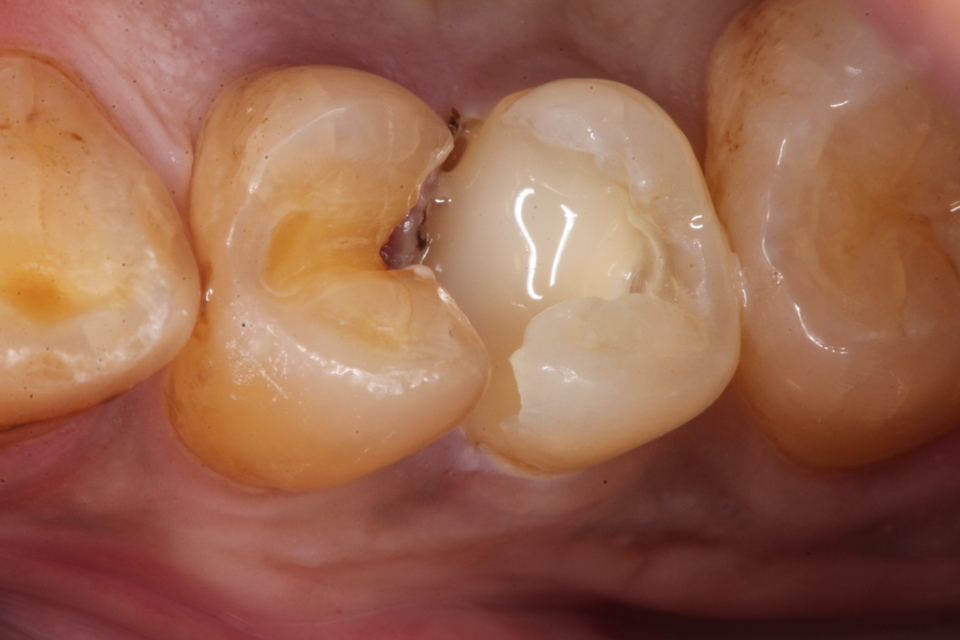

下顎7番の頬側歯茎部カリエスの原因 2025.06.04